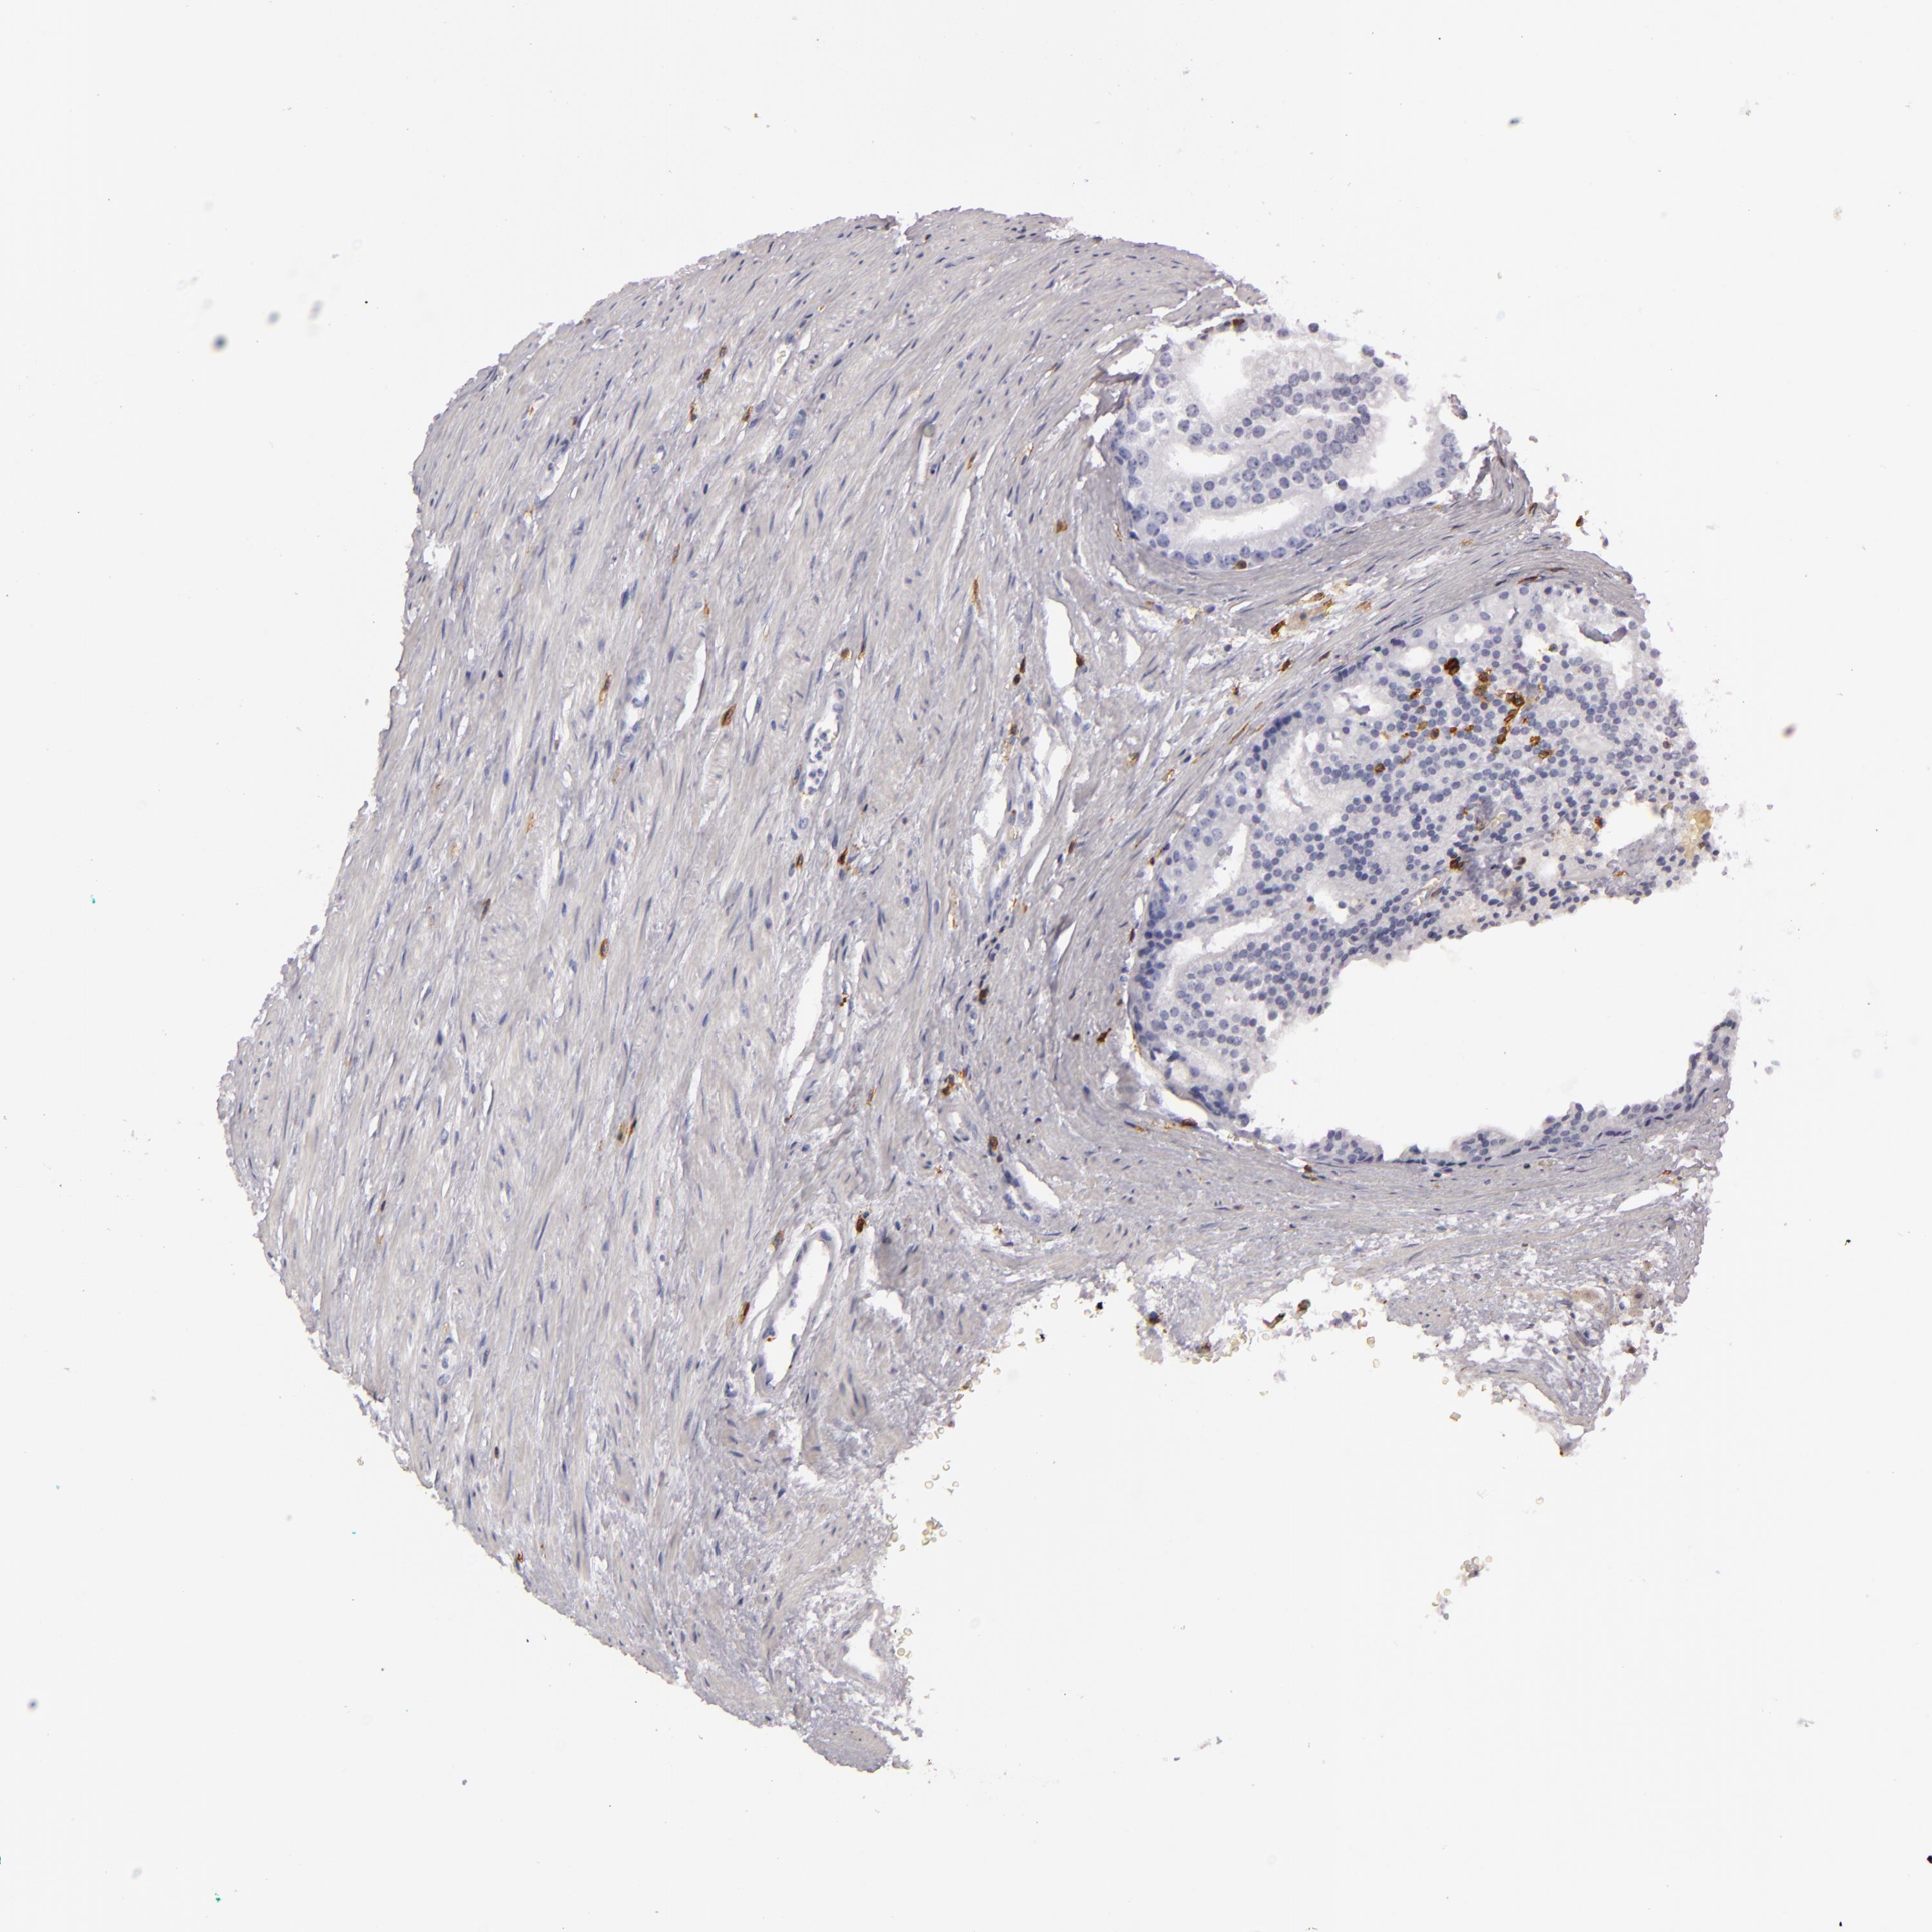

PROSTATE CANCER - Protein expressioni

A mouse-over function shows sample information and annotation data. Click on an image to view it in a full screen mode. Samples can be filtered based on level of antibody staining by selecting one or several of the following categories: high, medium, low and not detected. The assay and annotation is described here.

Antibody stainingi

Antibody staining in the annotated cell types in the current human tissue is reported as not detected, low, medium, or high, based on conventional immunohistochemistry profiling in selected tissues. This score is based on the combination of the staining intensity and fraction of stained cells.

Each image is clickable and will lead to virtual microscopy that enables deeper exploration of all samples and also displays staining intensity scores, fraction scores and subcellular localization as well as patient and tissue information for each sample.

Antibody HPA011157

Antibody CAB002223

Antibody CAB012978

Antibody CAB079960

Staining

High

Medium

Low

Not detected

Intensity

Strong

Moderate

Weak

Negative

Quantity

>75%

75%-25%

<25%

None

Location

Nuclear

Cytoplasmic/membranous

Cytoplasmic/membranous,nuclear

Adenocarcinoma, Low grade

Adenocarcinoma, High grade

Adenocarcinoma, Medium grade

Adenocarcinoma, NOS